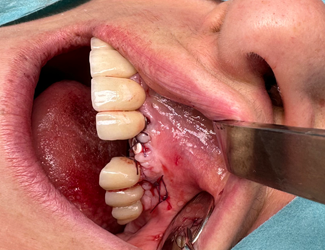

Yngre kvinne som mistet tenner 11-22 gjennom traume. Både en horisontal og vertikal defekt i et estetisk utfordrende område. En Yxoss 3D-printet membran produseres gjennom planleggingsverktøyet, i dette tilfellet IO-skanning og CBCT som grunnlag. En preprotetisk voksing på den tiltenkte suprakonstruksjonen produseres for å forutsi fremtidig protese og tiltenkt beinvolum. Partikulært bein påføres membranen som deretter fikseres på plass. Etter 6 måneders helbredelse fjernes membranen. Regenerert bein uten pseudoperiosteum er påvist, implantater kan plasseres med gode marginer og god protesetilstand.

Fjerning av ti-membranen avslører vitalt bein uten pseudo-periosteum